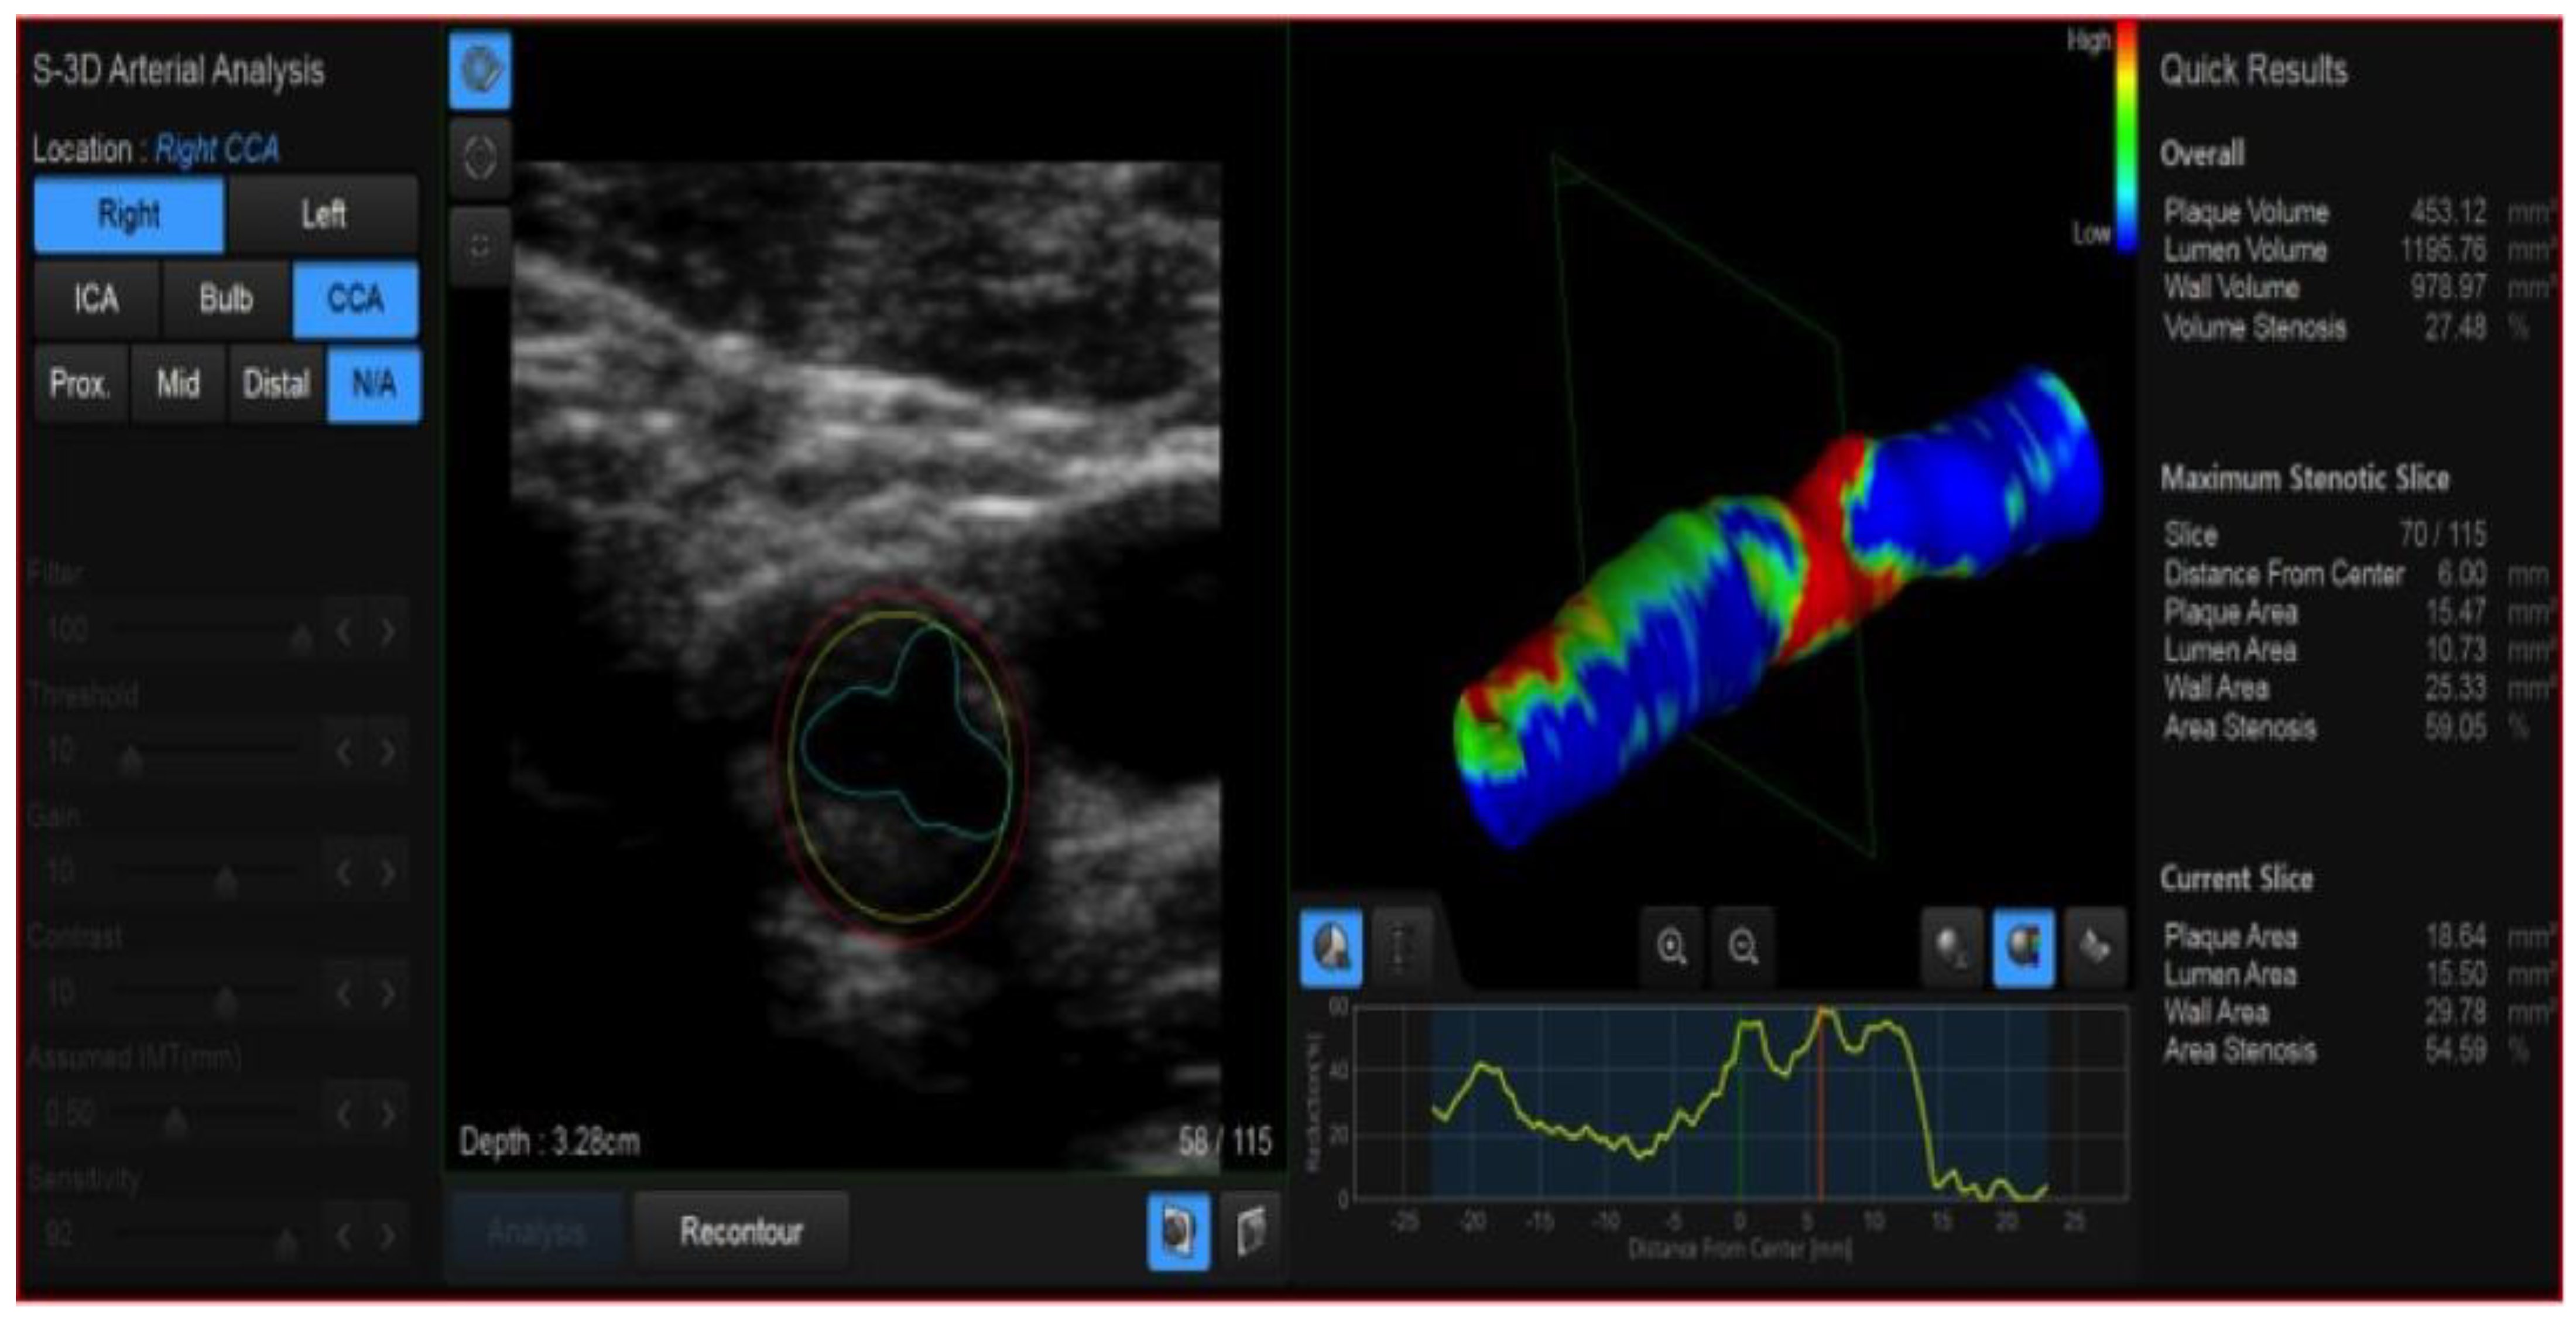

6. High Frame Rate Vector Flow (V-Flow) and 3D Arterial Analysis Ultrasound (3D-US)

- Fresilli, D.; Di Leo, N.; Martinelli, O.; Di Marzo, L.; Pacini, P.; Dolcetti, V.; Del Gaudio, G.; Canni, F.; Ricci, L.I.; De Vito, C.; et al. 3D-Arterial analysis software and CEUS in the assessment of severity and vulnerability of carotid atherosclerotic plaque: A comparison with CTA and histopathology. Radiol. Med. 2022, 127, 1254–1269. [Google Scholar] [CrossRef] [PubMed]

- Fenster, A.; Blake, C.; Gyacskov, I.; Landry, A.; Spence, J.D. 3D ultrasound analysis of carotid plaque volume and surface morphology. Ultrasonics 2006, 44 (Suppl. 1), e153–e157. [Google Scholar] [CrossRef]

- Sultan, S.R.; Bashmail, F.T.; Alzahrani, N.A.; Alharbi, S.I.; Anbar, R.; Alkharaiji, M. Is 3D ultrasound reliable for the evaluation of carotid disease? A systematic review and meta-analysis. Med. Ultrason. 2022; online ahead of print. [Google Scholar] [CrossRef]